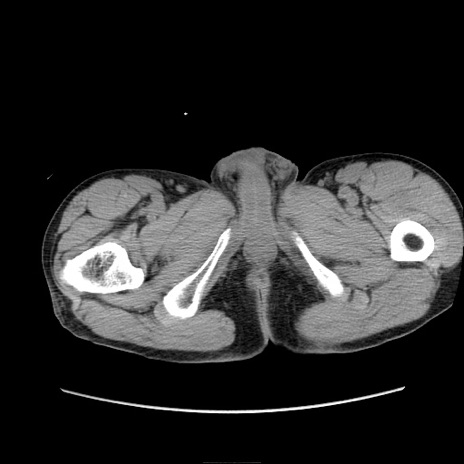

症例11(横断像)

【症例】 60歳代男性

【主訴】 下腹部痛

【現病歴】 本日夜中より下腹部痛の症状認め、受診。

【既往歴】 膀胱癌(膀胱全摘+尿管皮膚瘻術) 、胃癌術後

【身体所見】 BT 35.3℃、PR 58/min、BP 136/98mHg、腹部平坦、軟、腸蠕動音±、ストマ留置あり、左上腹部~正中部に圧痛あり、反跳痛なし。

【データ】WBC 5100、CRP0.01